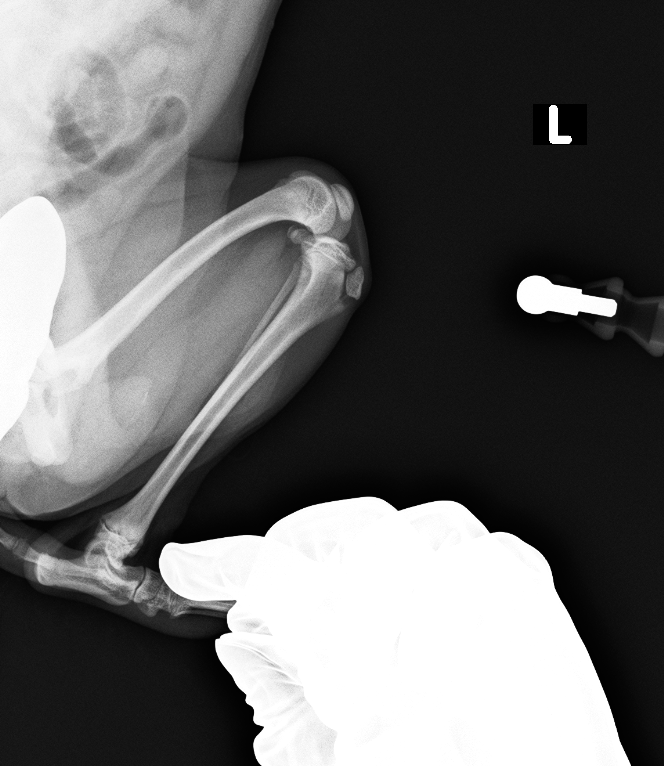

レントゲン検査より、脛骨粗面成長板の剥離

before